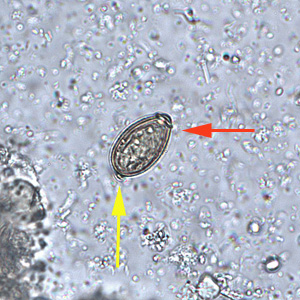

Case #235 – September, 2008

A 25-year-old man returned from three months of studying abroad in southeast Asia. Countries he visited during his studies included the Philippines, Indonesia and Thailand. Shortly after returning to the United States, he presented to his health care provider with abdominal pain, cramps and diarrhea. Due to the travel history, a routine ova and parasite (O&P) examination was performed on the patient’s stool. Objects A–F show objects observed in the formalin-concentrated stool specimen. All images were captured at 400x magnification. The object in Figure A measured approximately 70 micrometers long by 47 micrometers wide and was seen in large numbers. The objects in Figures B and E measured approximately 75 micrometers long by 60 micrometers wide and were seen in moderate numbers. The object in Figure C measured approximately 67 micrometers long by 38 micrometers wide and was seen in moderate numbers. The objects in Figures D and F measured approximately 25 micrometers long by 13 micrometers wide and were seen in rare numbers. What is your diagnosis? Based on what criteria?

Figure A